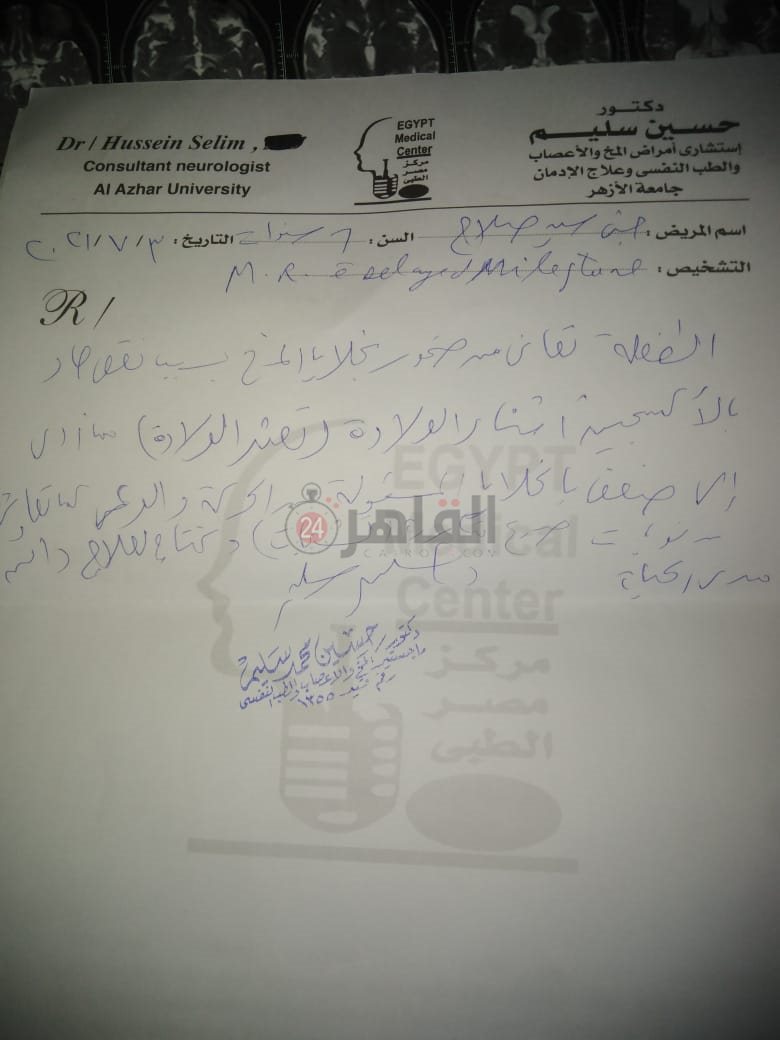

من جانبه، قال صلاح سيد، والد الطفلة جنى صلاح، إن ابنته تعاني من ضمور في المخ منذ ولادتها، نتيجة خطأ طبي، أدى إلى نقص كبير في الأكسجين لديها.

وأضاف في تصريحات خاصة لـ "القاهرة 24": "جنى تبلغ من العمر 6 سنوات، لا تستطيع المشي أو الوقوف على قدميها، نتيجة إصابتها بضمور في المخ منذ ولادتها".

وتابع: "مكنتش بتتحرك خالص، وجسمها طري، روحت كشفت عليها، وعملت أشعة وتحاليل كتير، أتأكدنا إصابتها بضمور في المخ"، مضيفًا:" مش بتعرف تأكل احنا اللي بنأكلها، هي عقلها كويس لكن مش بتتحرك ولا تتكلم".

وأوضح أن الطبيب الخاص بها أكد أن هناك داء خارج مصر يحسن من حالتها، ولكن باهظ الثمن، وتحتاج تناوله بشكل دوري.

واستكمل:" حاليًا تتناول أدوية شرب عادية، لحين توفيرالدولة علاجها من خارج مصر"، مشيرًا: "مفعتش قضية على الدكتور، ورضيت بقضاء ربنا".